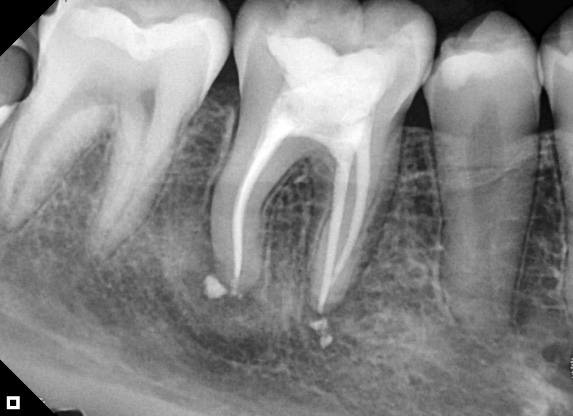

Electronic odontometry was carried out using an Airpex foraminal locator (Angelus). The working length was established at the foramen (zero of the electronic apex locator). Chemical-mechanical preparation was performed using rotary mechanized files. The gutta-percha cone was adjusted to the properly prepared canal (Figure 2). After conometry, each root canal received three applications of 1.7% trisodium EDTA and 2.5% sodium hypochlorite, which were potentiated for 30 seconds at 10% power using ultrasonic insert.

Figure 2: Conometry